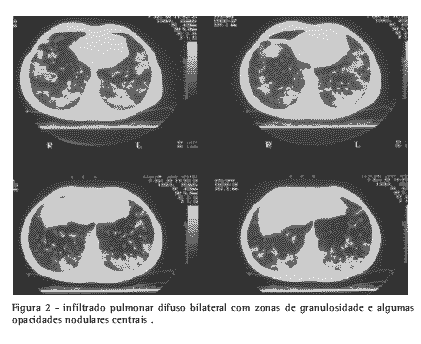

Estudo imagético: tomografia computadorizada de tórax com infiltrado pulmonar difuso bilateral, com zonas de granulosidade e algumas opacidades nodulares centrais. Não havia evidência de adenomegalias no mediastino (Figura 2).

Avaliação micológica: soromicologia com imunodifusão para H. capsulatum negativa; histopatologia: segmento de língula (obtido por biópsia pulmonar) corado por hematoxilina e eosina com granuloma tuberculóide com necrose caseosa e fibrose em parênquima pulmonar; técnica de Gomori-Grocott com metenamina argêntica com numerosos elementos leveduriformes pequenos ovóides e esferóides, unibrotantes, sugestivos de H.capsulatum; o exame de cultivo foi negativo.